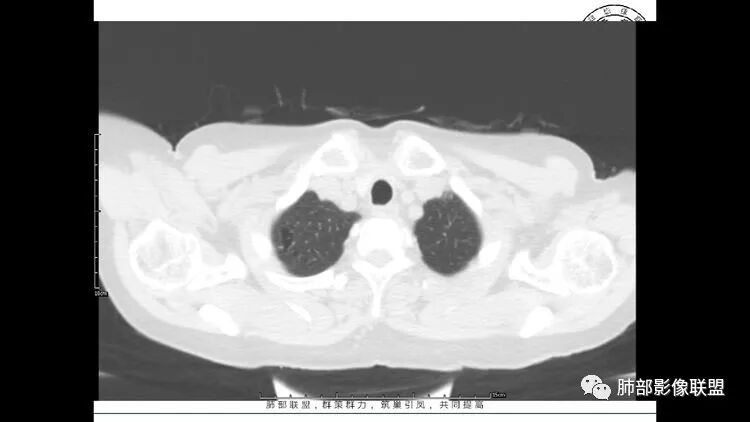

3.纵隔淋巴结肿大?,以主动脉弓为界向上向下增大。

王秀仙

双肺多发散在斑片状磨玻璃密度影及大小不等的薄壁含气囊腔,下肺相对较多较大。双肺多发结节,界清,边缘光滑,分叶不明显。右肺下叶前外基底段散在斑片树芽。前上纵膈偏左侧不规则软组织团块,密度不均,其内可见不规则纤维样低密度,周围簇状小淋巴结。考虑1淋巴细胞间质性肺炎。2考虑纵膈胸腺淋巴瘤。

前纵隔结节,附近小淋巴结